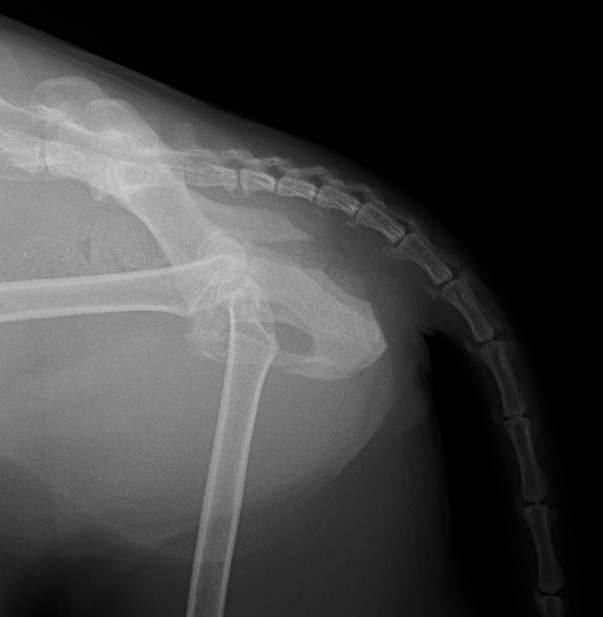

レントゲン検査で、左側の仙腸関節離断と同側の寛骨臼の骨折をしていることがわかりました。 寛骨臼の骨折は坐骨からの斜骨折を伴うもので、人の下顎骨骨折に用いられるMatrix Mandibleというプレートで整復しました。

手術前レントゲン側画像

レントゲン検査で、左側の仙腸関節離断と同側の寛骨臼の骨折をしていることがわかりました。 寛骨臼の骨折は坐骨からの斜骨折を伴うもので、人の下顎骨骨折に用いられるMatrix Mandibleというプレートで整復しました。

手術前レントゲン側画像